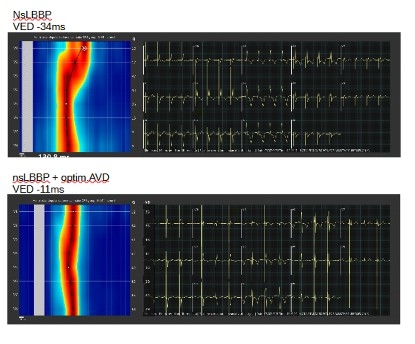

Metodika: Od začiatku júla 2025 recipienti CRT ako aj pacienti indikovaní na fyziologickú stimuláciu pre bradykardiu majú realizované UHF-EKG pred výkonom, periprocedurálne a vo vybraných prípadoch aj pri optimalizácii nastavenia prístroja po výkone. Na základe elektrických meraní a informácií z depolarizačných máp vyhodnocujeme komorovú aktiváciu pri LBBAP, BiV-CRT, LBBAP-CRT a LOT-CRT. Výsledky prezentujeme ako analýzu vlastných EKG záznamov z UHF-EKG a elektrofyziologického registračného systému, ktorý používame.

Výsledky: Naše iniciálne skúsenosti s využitím UHF-EKG pri výkonoch naznačujú, že pri stimulácii v oblasti ľavého ramienka sme úspešnejší v dosahovaní skutočne fyziologickej aktivácie komôr a exaktnejší v správnom vyhodnocovaní typu stimulácie (LVSP vs LBBP). Pri CRT nám uľahčuje rozhodovací proces pri výbere optimálneho spôsobu resynchronizácie individuálne pre každého pacienta (BiV vs LBBAP-CRT alebo ich kombináciu ako LOT-CRT). U týchto pacientov je zároveň neinvazívne a jednoducho možné vyhodnotiť elektrický substrát komorovej dyssynchronie a odlíšiť "pravú" blokádu ľavého Tawarovho ramienka od nešpecifickej vnútrokomorovej poruchy vodivosti (IVCD).